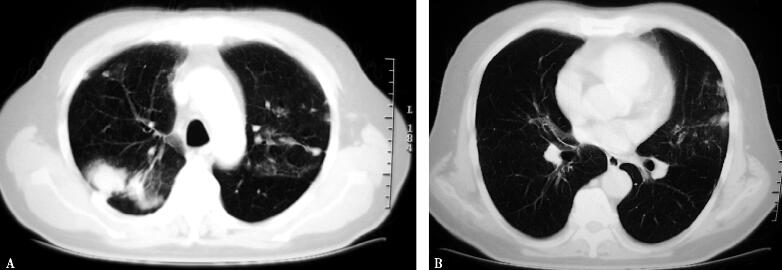

体检发现肺部阴影3天(图1 A肺窗,B纵隔窗)。

图1

患者为中年男性,体检时胸部CT发现肺部异常。由于患者无明显的临床症状,因此胸部影像特点成为我们分析疾病的首要切入点。通过阅片发现,患者的肺部病灶主要表现为双肺多发的结节影,结节大小不一,分布于中上肺野近胸膜处,密度较高,且较均匀。针对上述影像学表现,可能的病因既可以是肺部感染性疾病(细菌、结核、曲霉菌病等),也可以是非感染性疾病(肿瘤、结节病、风湿性疾病等系统性疾病的肺部表现)。因此在问诊时除了注重肺部疾病所导致的呼吸系统症状的同时,还要兼顾系统性疾病的全身表现。而判断感染和非感染也正是我们首先需要考虑的问题。